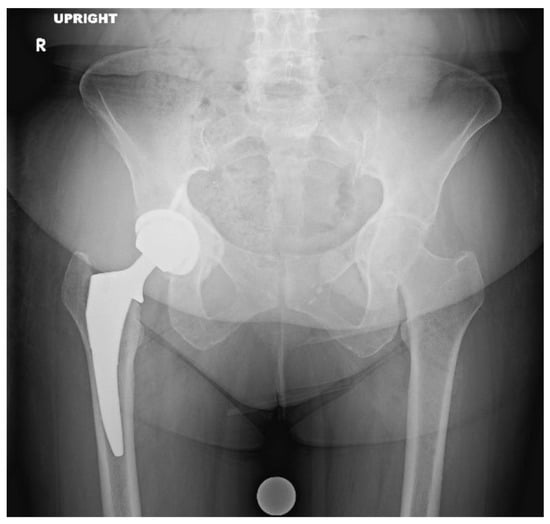

| Class | Ilioischial Line | Iliopectineal Line | Recommended Treatment |

|---|---|---|---|

| I | Intact (femoral head medialized) | Intact | Implant Placement: Lateralization of acetabular component to match native rim. Standard component needed, no need for screw augmentation. Bone graft: Not likely required. |

| II | Violated | Intact | Implant Placement: Lateralization of acetabular component to rim, consider use of larger or jumbo component. Screw fixation optional. Consider lateralized acetabular liner. Bone Graft: Likely required medially with impaction grafting. |

| III | Violated | Violated | Implant Placement: Lateralization of acetabular component, consider use of jumbo, deep profile, revision, or multi-hole component. Screw fixation is strongly recommended in multiple planes to augment construct stability. Consider lateralized acetabular liner. Bone Graft: Universally required. Autograft reamings and morselized cortical bone from native head is recommended, consider use of additional allograft bone to fill large defects. Powdered antibiotic can be added to graft mixture to reduce risk of prosthetic joint infection. |